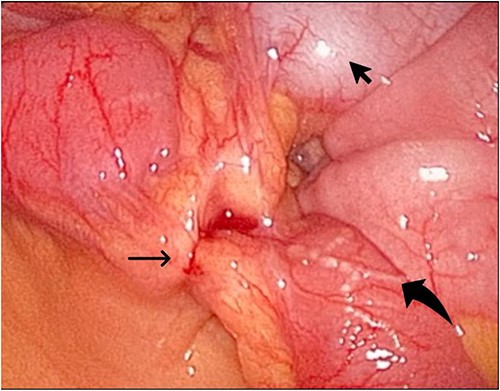

During her hospital stay, the patient showed no improvement regarding abdominal pain, nausea, or abdominal exam. Therefore, she was offered a laparoscopic exploration to verify the diagnosis of a FB to which she agreed. She was taken to the operating room, and the exploration showed an inflammatory process in the LLQ (Fig. 3) with the sigmoid colon attached to the area of the inflammatory reaction. A FB was found in the mesentery of two loops of the ileum 100 cm from the ileocecal junction (Figs 4 and 5). Removal of the FB safely and milking of the small bowel showed no leakage of bowel contents (Fig. 6). And, exploring the rest of the abdomen showed no other pathology and normal ovaries (Figs 7 and 8); the procedure was uneventful. The FB was identified as a toothpick, 3 cm in length (Fig. 9).

The laparoscopic exploration showed a FB in the mesentery of two loops of the ileum 100 cm from the ileocecal junction—after full exposure of the site of the toothpick.